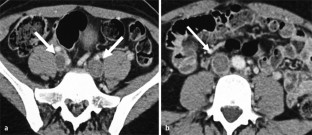

Abb. 6

Abb. 7